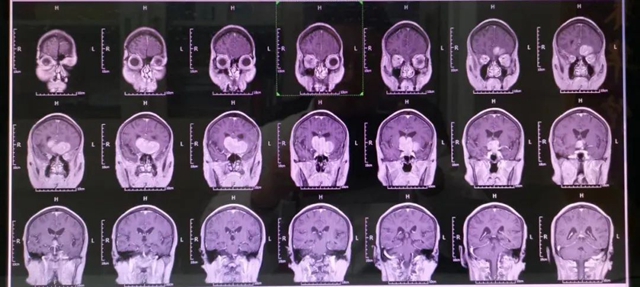

2020年,四川省自贡市70多岁的付大爷突然昏迷,摔伤额头,当地医院头颅CT发现颅内存在巨大占位性病变,转入西南医科大学附属中医医院神经外科进一步诊治,头颅MRI显示脑袋正中偏左的鞍区处有一个“胎儿”样的巨大肿瘤。

由于鞍区肿瘤与周围脑组织特别是下丘脑紧密相邻手术难度很大,一般难以全切,术后复发率高。

术前

术后

神经外科手术团队针对肿瘤位置和术后康复多次术前讨论,反复思考手术入路。

较好的显露鞍区及鞍旁组织结构,针对术后易出现内分泌紊乱、低钠血症等问题认真分析,制定精细的康复治疗方案。即行神经颅内镜辅助显微镜下鞍区巨大占位切除术,历时6小时,肿瘤被完全切除,解除了肿瘤对视神经、视交叉及其他神经、血管的压迫。

术后一周后,付大爷双眼视力逐渐好转,各项生命体征平稳。家属感叹不已:“4年来,老人视力越来越差,经常头晕头痛,一直认为是白内障,现在终于放心了。”